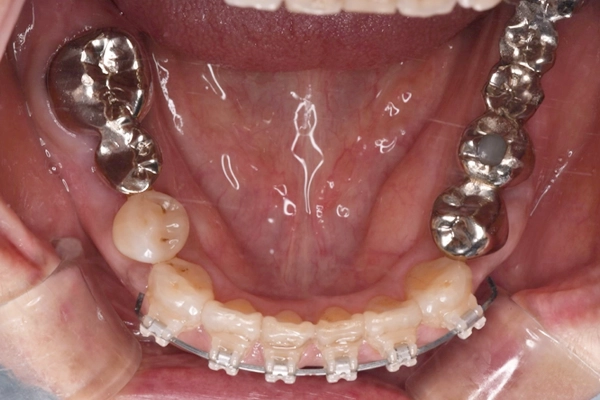

治療前の上顎の様子

です。

矯正を行ったことで、上顎のアーチも整ってきていることがわかります。

治療前の下顎の様子

矯正を行ったことで、前歯のガタガタ綺麗にすることができました。